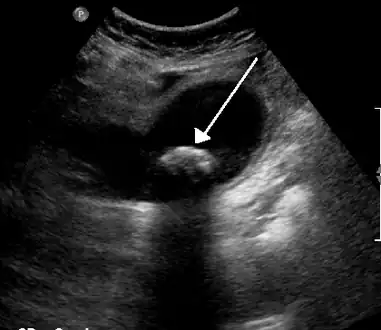

On abdominal ultrasound, sinking gallstones usually have posterior acoustic shadowing. In floating gallstones, reverberation echoes (or comet-tail artifact) is seen instead in a clinical condition called adenomyomatosis. Another sign is wall-echo-shadow (WES) triad (or double-arc shadow) which is also characteristic of gallstones.[38]

A 1.9 cm gallstone impacted in the neck of the gallbladder and leading to cholecystitis as seen on ultrasound. There is 4 mm gall bladder wall thickening.